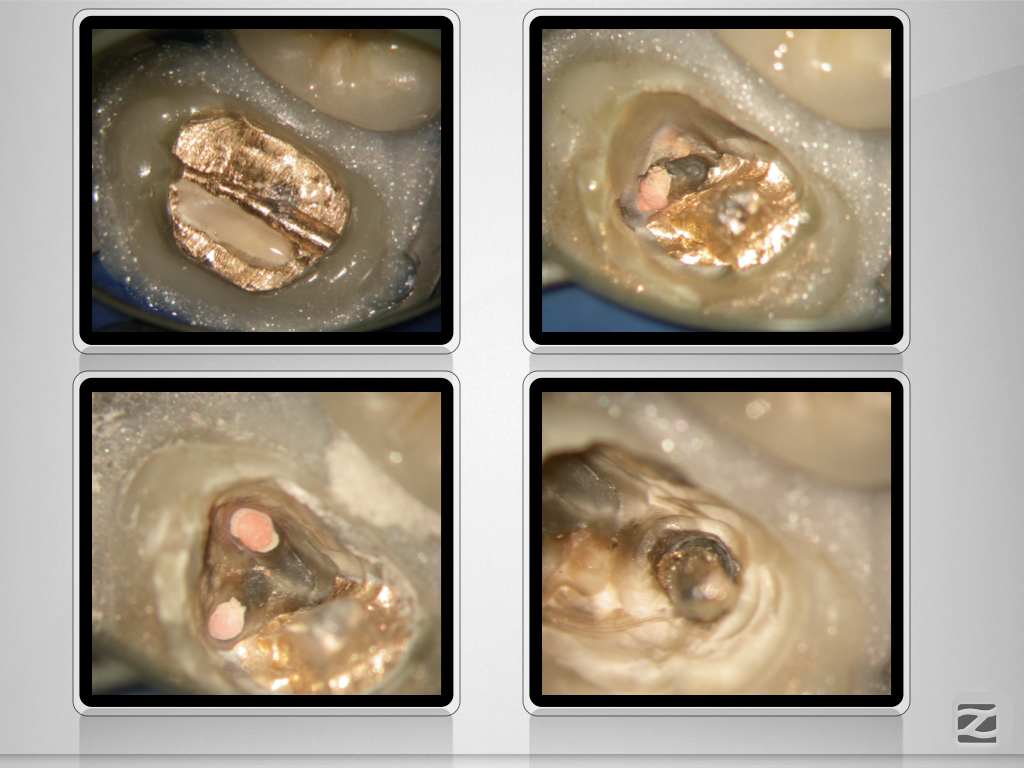

27D.002 Veröffentlicht 18. Januar 2020 am 1024 × 768 in Wer hat Angst vor’m bösen Stift? Teil 1 , Metallstift